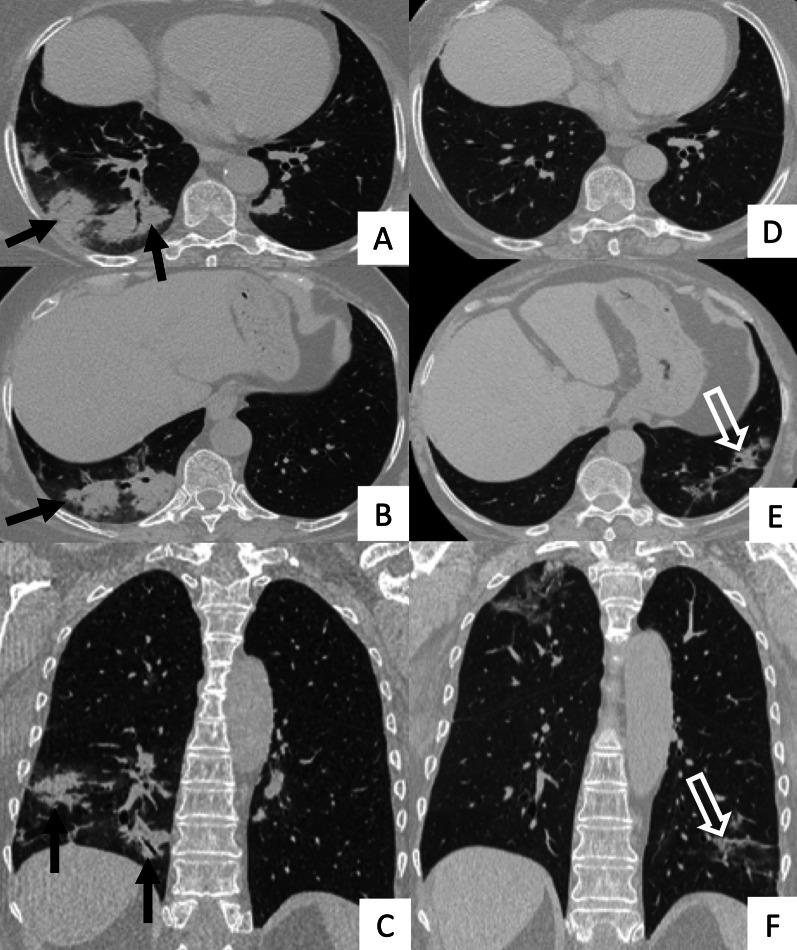

Connective tissue diseases (CTDs) include a spectrum of disorders that affect the connective tissue of the human body; they include autoimmune disorders characterized by immune-mediated chronic inflammation and the development of fibrosis. Lung involvement can be misdiagnosed, since pulmonary alterations preceded osteo-articular manifestations only in 20% of cases and they have no clear clinical findings in the early phases. All pulmonary structures may be interested: pulmonary interstitium, airways, pleura and respiratory muscles. Among these autoimmune disorders, rheumatoid arthritis (RA) is characterized by usual interstitial pneumonia (UIP), pulmonary nodules and airway disease with air-trapping, whereas non-specific interstitial pneumonia (NSIP), pulmonary hypertension and esophageal dilatation are frequently revealed in systemic sclerosis (SSc). NSIP and organizing pneumonia (OP) may be found in patients having polymyositis (PM) and dermatomyositis (DM); in some cases, perilobular consolidations and reverse halo-sign areas may be observed. Systemic lupus erythematosus (SLE) is characterized by serositis, acute lupus pneumonitis and alveolar hemorrhage. In the Sjögren syndrome (SS), the most frequent pattern encountered on HRCT images is represented by NSIP; UIP and lymphocytic interstitial pneumonia (LIP) are reported with a lower frequency. Finally, fibrotic NSIP may be the interstitial disease observed in patients having mixed connective tissue diseases (MCTD). This pictorial review therefore aims to provide clinical features and imaging findings associated with autoimmune CTDs, in order to help radiologists, pneumologists and rheumatologists in their diagnoses and management.

结缔组织病(CTDs)包括一系列影响人体结缔组织的疾病;它们包括以免疫介导的慢性炎症和纤维化发展为特征的自身免疫性疾病。肺部受累可能会被误诊,因为肺部改变仅在20%的病例中先于骨关节炎表现出现,且在早期阶段没有明确的临床发现。所有肺部结构都可能受累:肺间质、气道、胸膜和呼吸肌。在这些自身免疫性疾病中,类风湿关节炎(RA)的特征是普通型间质性肺炎(UIP)、肺结节和伴有空气潴留的气道疾病,而系统性硬化症(SSc)常表现为非特异性间质性肺炎(NSIP)、肺动脉高压和食管扩张。NSIP和机化性肺炎(OP)可见于多发性肌炎(PM)和皮肌炎(DM)患者;在某些情况下,可观察到小叶周围实变和反晕征区域。系统性红斑狼疮(SLE)的特征是浆膜炎、急性狼疮性肺炎和肺泡出血。在干燥综合征(SS)中,HRCT图像上最常见的表现是NSIP;UIP和淋巴细胞间质性肺炎(LIP)的报道频率较低。最后,纤维化NSIP可能是混合性结缔组织病(MCTD)患者中观察到的间质性疾病。因此,本图像综述旨在提供与自身免疫性CTDs相关的临床特征和影像学表现,以帮助放射科医生、呼吸科医生和风湿病科医生进行诊断和管理。